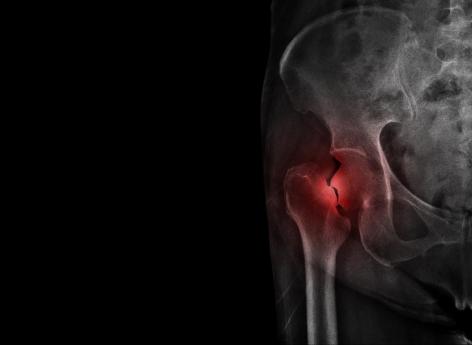

Dite "silencieuse", l'ostéoporose est une maladie osseuse particulièrement difficile à diagnostiquer, notamment parce qu'elle touche en majorité des personnes – principalement des femmes ménopausées – âgées de plus de 50 ans. Perte de taille de 4 centimètres, douleurs aigües… Certains symptômes permettent néanmoins d'amener le patient sur la voie du dépistage. Parmi eux figure la fracture de la hanche chez l'un des parents, puisqu'elle constitue un risque héréditaire.

Ainsi, interroger sa famille sur son historique de fractures est primordial dans le dépistage et le suivi de l'ostéoporose. Lorsqu'une patiente dont l'un des parents a eu une fracture de la hanche est ménopausée, donc sujette à l'ostéoporose, il est indiqué qu'elle consulte son médecin afin de se faire prescrire une densitométrie osseuse. Cet examen, fiable, rapide, et peu irradiant, permet de déterminer la résistance osseuse, donc de prédire le risque de fracture. Une étape indispensable, selon la docteure Karine Briot.

La professionnelle de santé prend l'exemple d'une patiente dont la mère s'est fracturé le col du fémur ; à ce facteur de risque peuvent s'en ajouter d'autres, comme la vieillesse, puisque l'âge moyen des fractures de la hanche se situe aux environs de 25 ans. Conséquence : en fonction du nombre ou de l'importance des facteurs, le médecin peut prédire le risque de fracture à 5 ou 10 ans.